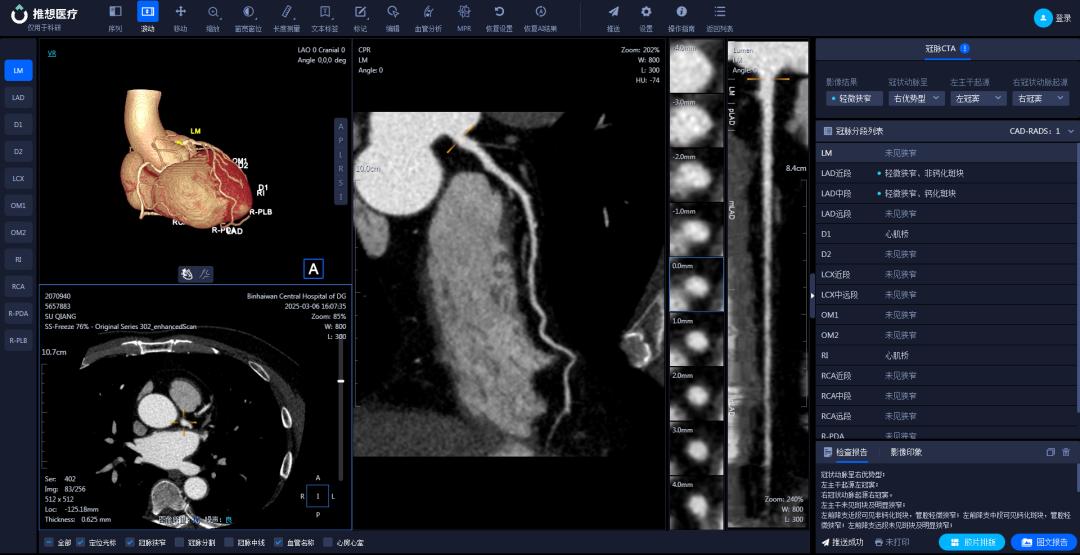

在医学影像科,AI辅助诊断系统宛如一位经验丰富且不知疲倦的医学影像专家,可快速分析肺结节、钼靶检查、骨疾病(骨折)、脑梗塞、脑出血、冠脉CTA(冠状动脉CT血管造影)等影像,提供精准诊断参考,助力医生“一秒读片”。

结合AI技术,256排CT实现去金属伪影、智能心脏重建、一键式卒中流程管理等功能,为心血管疾病和脑卒中患者争取黄金救治时间。